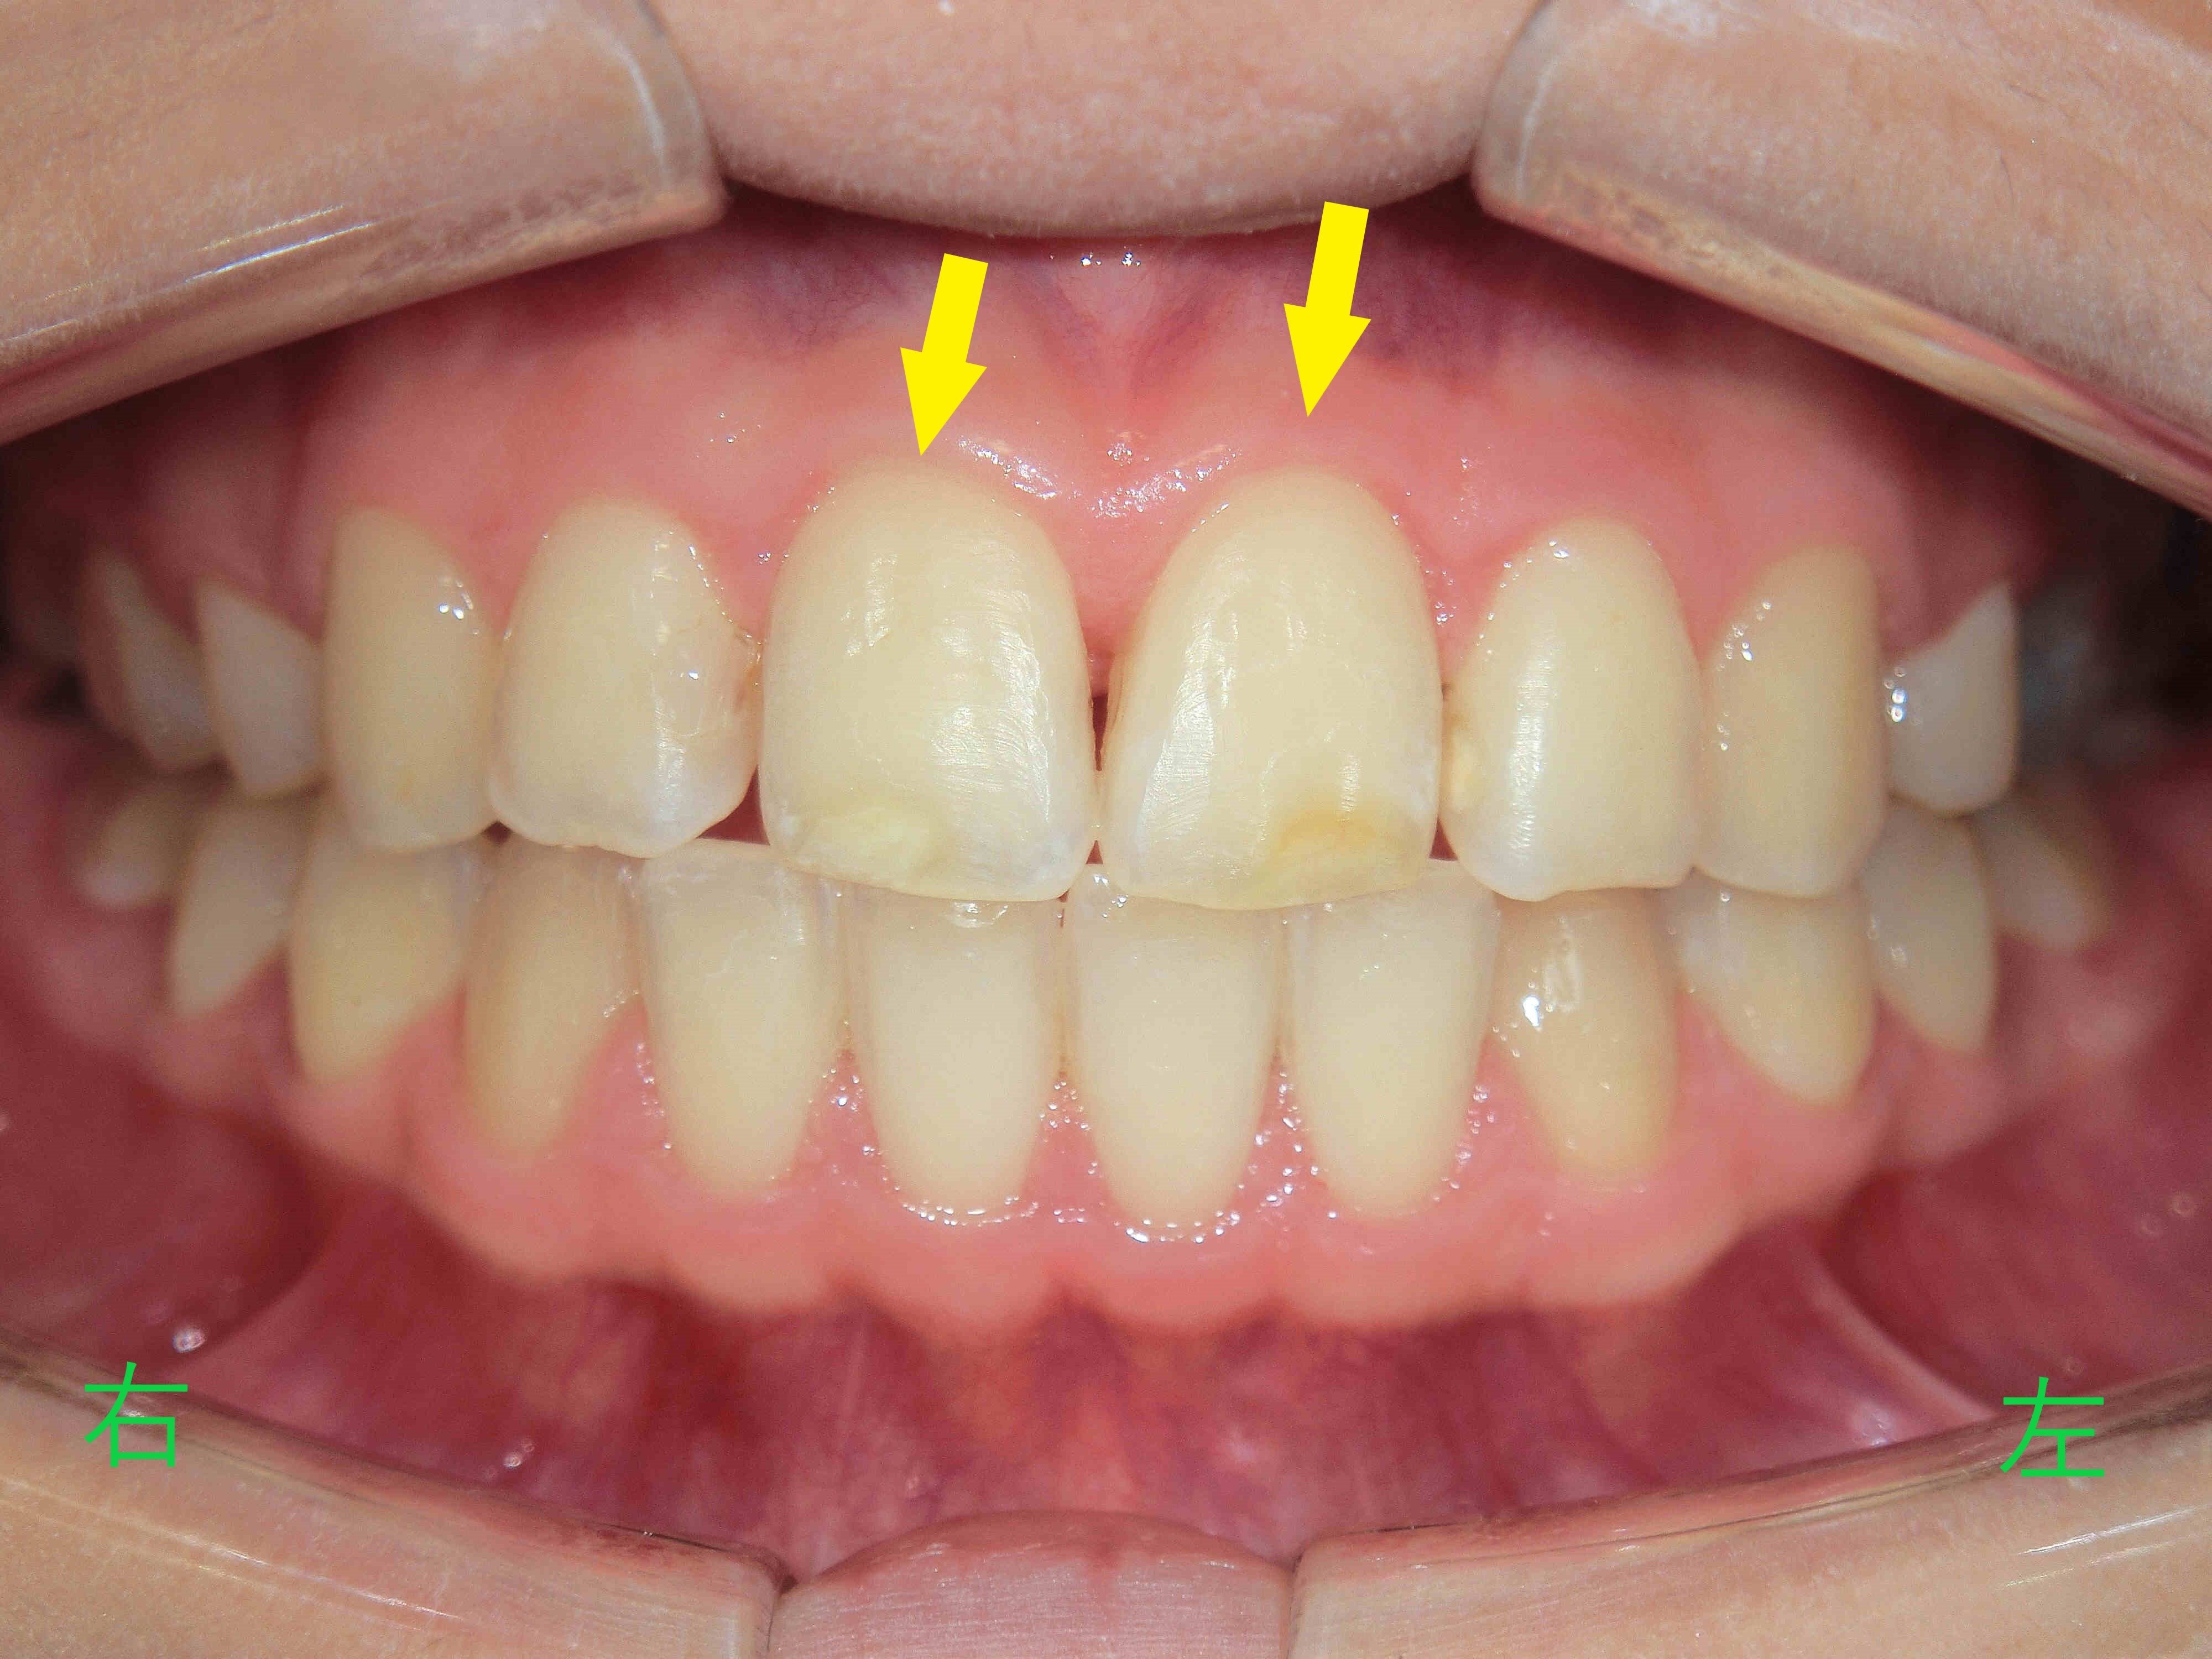

上顎前歯(黄色矢印)が後方へ移動したことで、初診時に訴えがあった前突感(いわゆる出っ歯)は改善されました。

また、患者様は治療前には力を入れないと口を閉じることが難しかった状態から、現在では自然に口を閉じられるようになり、結果に満足されているご様子でした(※個人の感想です)。

治療前と治療後の口腔内写真を比較すると、上顎前歯が後方へ移動し、下顎前歯との接触が確認できます。また、治療前はV字型であった歯列が、治療後はU字型に改善されています。

今回の症例では、矯正治療により口元の印象も大きく変化し、自然に口を閉じることが可能となりました。